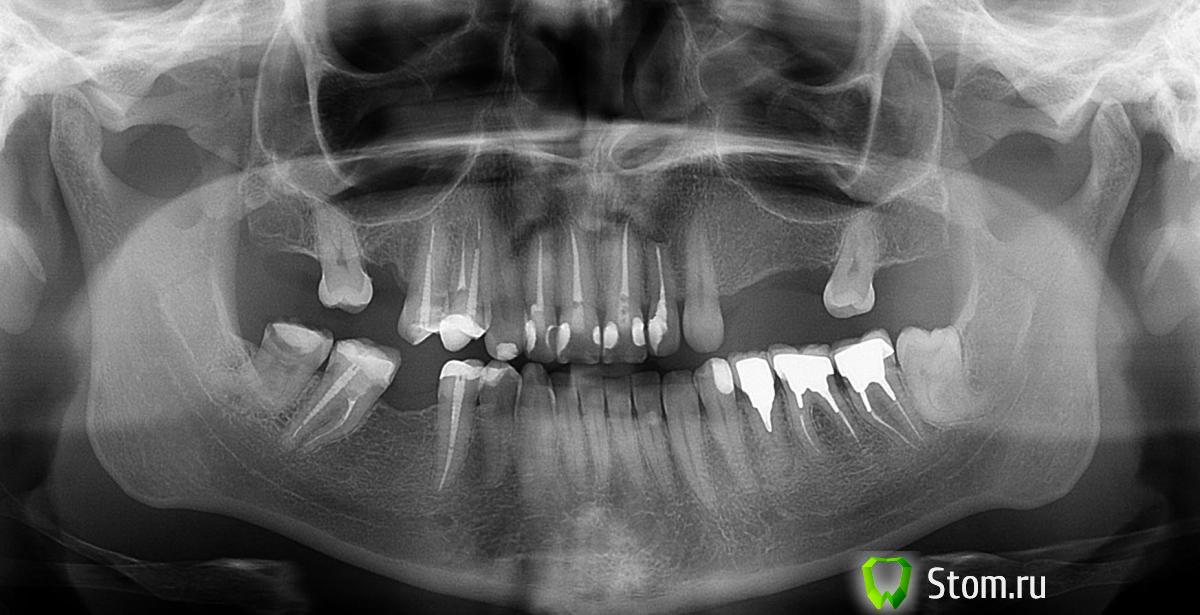

Afffinity Опубликовано 15 февраля, 2012 Поделиться Опубликовано 15 февраля, 2012 Если да, то17 депульпировать, 15 желательно перелечить и востановить внутрикорневой вкладкой, 23-27 слишком большой дефект для мостовидного протеза, здесь лучше прибегнуть к имплантации.45-47 перелечить, востановить ВКВ, далее мостовидный протез Ну а совсем дешево и сердито - съемный протез хД 1 Ссылка на комментарий

Tasadik Опубликовано 15 февраля, 2012 Автор Поделиться Опубликовано 15 февраля, 2012 (изменено) Спасибо большое что откликнулись. Имплантация очень даже рассматривается.Но хватит ли места для импланта 16зуба? Вместо 24,25,26 зуба можно установить два импланта или обязательно все три?И отдельный вопрос про фронтальные зубки. Верхние 12,11,21,22, в композите. Очень хочу красивые зубки. Чем лучше их сделать? Перелечь+штифт+безметал или перелечить +вкладка(какая?) +безметал?Нижние фронтальные стесаны не красиво. И хочется поднять немного прикус. Чем и как? Виниры или коронки?Зубки живые, пилить жалко.47,45 недавно подготовили под коронки, они пролечены. Плохо? Возможно ли с ними такой план. Там мало кости, сделать подсадку и на пол года установить мост на 47-45, потом снять и уже установить имплант. Изменено 15 февраля, 2012 пользователем Tasadik Ссылка на комментарий

Alexandr dantist Опубликовано 15 февраля, 2012 Поделиться Опубликовано 15 февраля, 2012 Для 16 места не хватит, нужно соседей подвинуть. Если хотите все в порядок привести, сначала ортодонтия, обеспечить место под имплантацю. Перелечить 15,22, остальное под прицельными снимками посмотреть надо. Передние зубы- заменить пломбы если необходимо,безметал без вкладок и штифтов.24,25,26 достаточно и двух имплантатов.В области 45,47 высота выглядит достаточной, о ширине можно судить только по КТ.Если уж занялись, чтобы потом подольше к стоматологу не ходить 35 тоже изучить под прицельными снимками и перебрать, либо удалить/имплантат. Ссылка на комментарий

Tasadik Опубликовано 23 февраля, 2012 Автор Поделиться Опубликовано 23 февраля, 2012 (изменено) Нужен ваш совет! Для имплантации мне настоятельно рекомендуют импланты фирмы Астра(Швец.) , ругают Нобель за уход кости в районе шейки импланта и сильный запах из-за негерметичного полого тела, чего нет у Астры. Прокомментируйте пжл это утверждение, меня берут сильные сомнения. Нобель часто хвалят, с таким мнением столкнулась впервые.КТ показало что кости достаточно, предлагается закрытый синус-лифт с одновременной установкой трех имплантов 24,25,26 Два импланта также настоятельно не рекомендуется мне т.к. это ВЧ. Я планировала два. Изменено 23 февраля, 2012 пользователем Tasadik Ссылка на комментарий